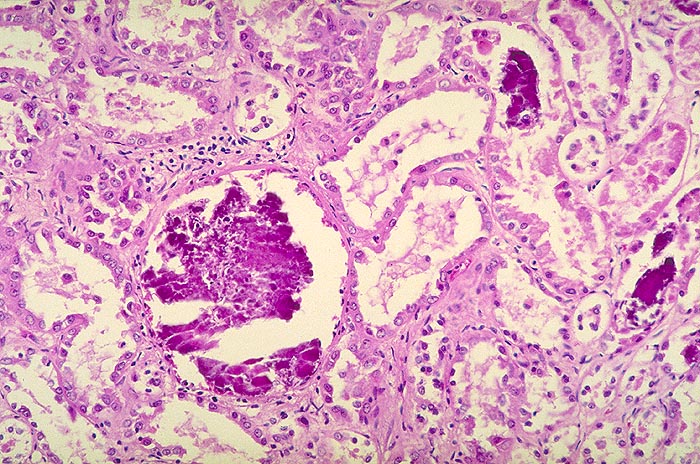

Nephrokalzinose, dystrophe Form

Massive Verkalkungen von teilweise nekrotischen Tubulusepithelien und vollständige Verkalkung eines Glomerulus.

Zufallsbefund in einer Transplantatbiopsie wenige Tage nach Transplantation.

Nekrotische Tubuli und Glomeruli mit Verkalkungen. Kalkablagerungen bei Überschuss alkalischer Valenzen z.B. Nekrosen. Nephrokalzinose tritt auch bei normalen Serumkalziumwerten auf, wird aber durch Hyperkalziurie begünstigt.